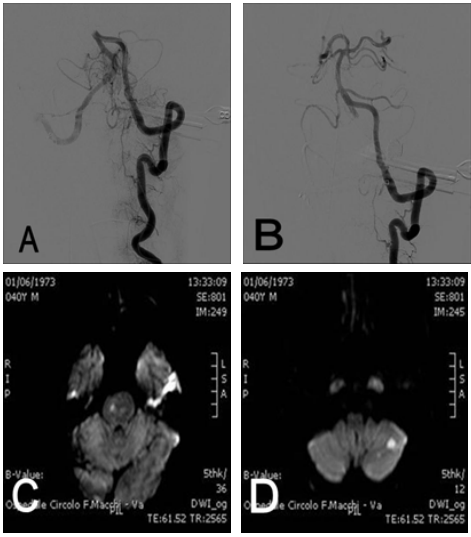

Figure 1 Digital subtraction angiography of basilar artery occlusion before (A) and after (B) treatment with mechanical thrombectomy. MRI sequences in DWI show a pontal (C) and cerebellar (D) ischemia.

Endovascular treatments were performed within 8 hours of stroke onset (mean time 4 hours, range 2-6) by an Interventional neuroradiologist. Under local anesthesia using a transfemoral approach, a 6 French guide catheter was placed in the proximal vertebral artery. To prevent the occurrence of a thromboembolic event during the procedure, a solution of 2000 international units heparin and 0.9% normal saline (1000mL) were administered in continuous through the guiding catheter. A cerebral diagnostic angiography was performed to assess vessel occlusion and collateral flow to the affected vessel territory. After basilar arterial occlusion was demonstrated, diagnostic catheter was exchanged with a 6F guide catheter (Neuron, Penumbra, California, USA). A microcatheter on a microwire 0.018-inch (Rebar 18, Covidien, California, USA) was introduced into the target vessel. After that, a retrievable stent (in 5 cases Solitaire, Covidien, California, USA; in other 2 cases Revive, Codman, California, USA) was introduced through microcatheter and deployed across the occluded segment. (Figure 1 & 2) After the stent was maintained in place for least 3 minutes, microcatheter and stent were gently pulled back together and withdrawn outside the body through the guide catheter. A control angiogram was performed to assess status of recanalization and possible distal embolic events. If recanalization was unsuccessful, the procedure was repeated, with a maximum of 4 was allowed. In addition to mechanical thrombectomy two patients received an intra-arterial thrombolysis (IAT) with recombinant tissue-plasminogen activator (rt-PA) (60ml and 15ml respectively of Alteplase, ActyliseÒ) and one patient received intra-venous rt-PA thrombolysis (72ml - 0,9ml/kg - of Alteplase, ActyliseÒ) (Table 1 & 2). Recanalization was classified according to the Thrombolysis in Cerebral Infarction (TICI) grading scale.13 TICI grades 3 and 2b were rated as sufficient recanalization and TICI grades 2a to 0 were rated as insufficient. In two cases it was reported a slowdown of circle in the right posterior cerebral artery treated by an intravenous injection of 500mg of acid acetylsalicylic (FlectadolÒ). All patients after procedure were observed for at least 24 hours in an intensive care unit and CT was performed. The NIHSS score was assessed at day 7 by a stroke neurologist. Clinical outcome was assessed at 3 months by a stroke neurologist according to the modified Rankin Scale (mRS) score.14